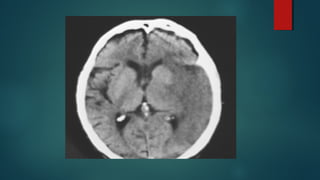

Este documento es el programa para un taller de imágenes del curso de emergencia 2015 impartido por el Dr. Víctor Delgado. El taller se centra en el uso de imágenes médicas para el diagnóstico y tratamiento de pacientes en coma traumático según la base de datos de Marshall. El Dr. Delgado es el único instructor repetido a lo largo del documento.